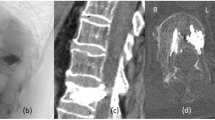

The vertebral artery and the cervical spine are closely related anatomically, but damage to that vessel in cervical spinal injury and subsequent stroke involving the vertebrobasilar distribution has rarely been reported. A case of vertebrobasilar stroke following traumatic injury to the cervical spine is described. The anatomy of the vertebrobasilar system is reviewed and possible mechanisms of injury discussed. A literature review follows.